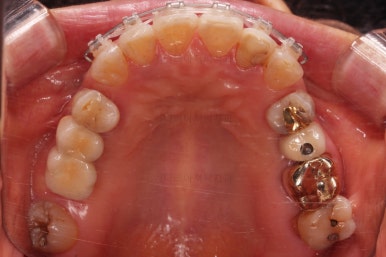

초진 시 입안의 모습입니다.

일반적인 교정을 하기에는 적합한 모습은 아니었어요.

치아는 군데군데 없고 임플란트도 있고 브릿지로 연결된 치아도 있으며 전반적인 잇몸 상태도 좋지 못했어요.

앞니가 벌어져 있고 뻗쳐 있으며 잇몸에서 쏙 빠져나와 있는 듯한 느낌이었어요.